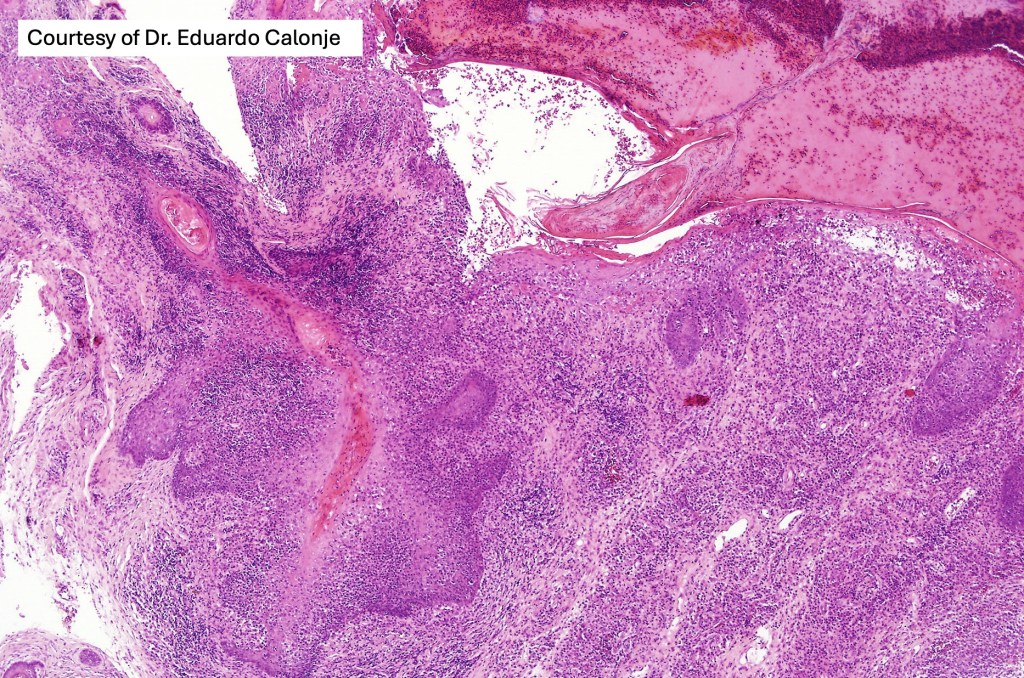

Histological features

•Epidermal involvement often absent

•Follicular infiltration by atypical lymphocytes & Sézary cells

•+/- syringotropic lesions

•Granulomatous inflammation secondary to follicular destruction